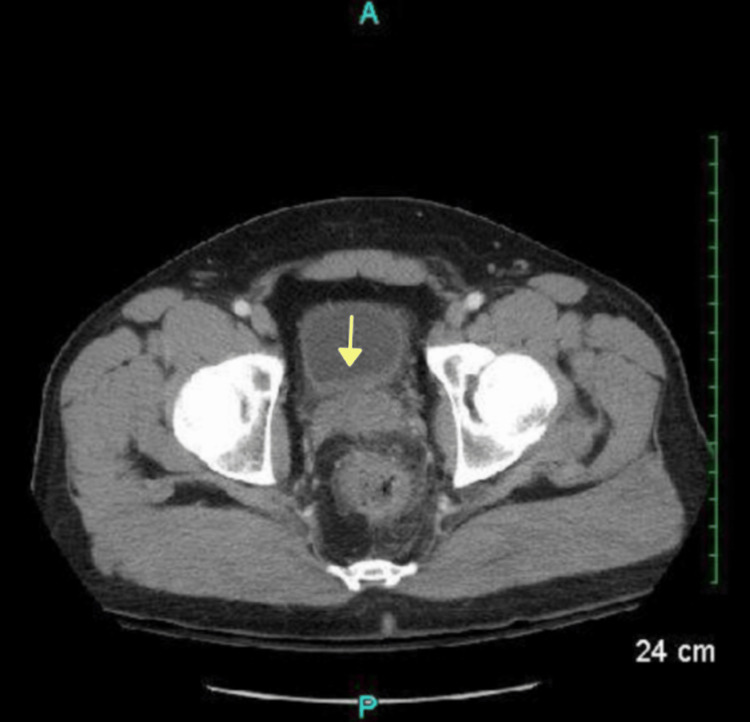

Additional pockets of air and an irregular hyper-dense nodular material were found in the anterior bladder along with diffuse urinary bladder wall thickening, suggestive of a CVF (Figure 3).

The pathology report confirmed the presence of diverticula with focal chronic inflammation, fibrosis, focal hemorrhage, and reactive changes (Figure 4). No perforation was seen.